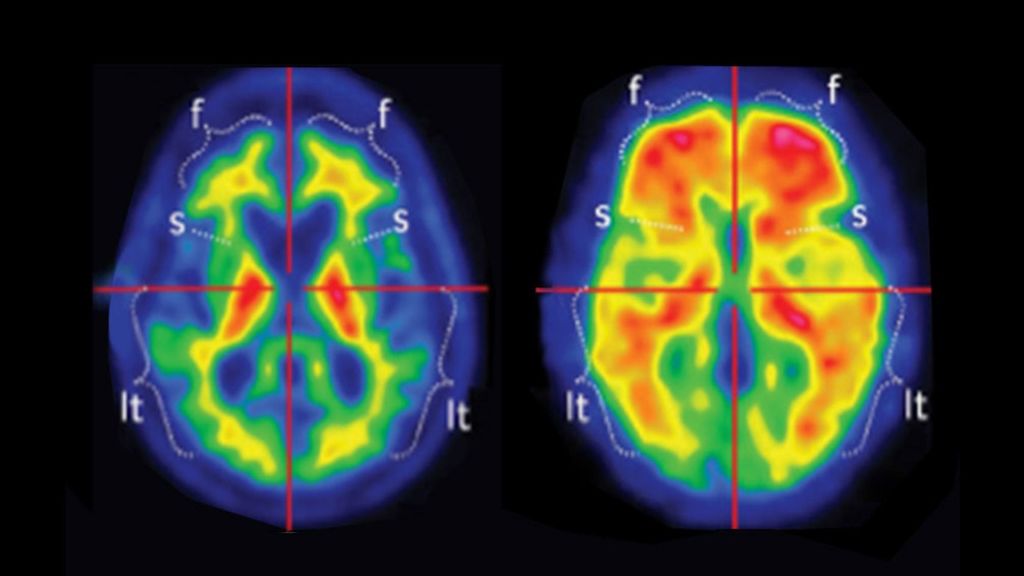

Los investigadores analizaron la actividad génica en el córtex prefrontal dorsolateral, una de las primeras regiones afectadas en la enfermedad de Alzhéimer, en muestras de tejido post mortem de 450 personas y obtuvieron un mapa detallado de la variación en el procesado alternativo del ARN. Este mapa permitió, en primer lugar, descubrir cientos de alteraciones en el procesado del ARN mensajero asociadas a la enfermedad de Alzhéimer y su patología. Además, al contrastar la información del procesado alternativo con aquella correspondiente a la variación genética los investigadores elaboraron un catálogo de variantes genéticas que influyen el procesado alternativo del ARN mensajero de más de 3.000 genes en tejido cerebral. Los investigadores también llevaron a cabo un estudio de asociación con información de transcripción y procesado alternativo respecto a la presencia o ausencia de enfermedad. Este análisis permitió identificar 21 genes relacionados con la enfermedad de Alzheimer, ocho de ellos sin previa relación la enfermedad.  Estos genes apuntan, entre otras rutas moleculares, a una participación de aquellas relacionadas con la degradación y reciclaje de proteínas en la enfermedad.